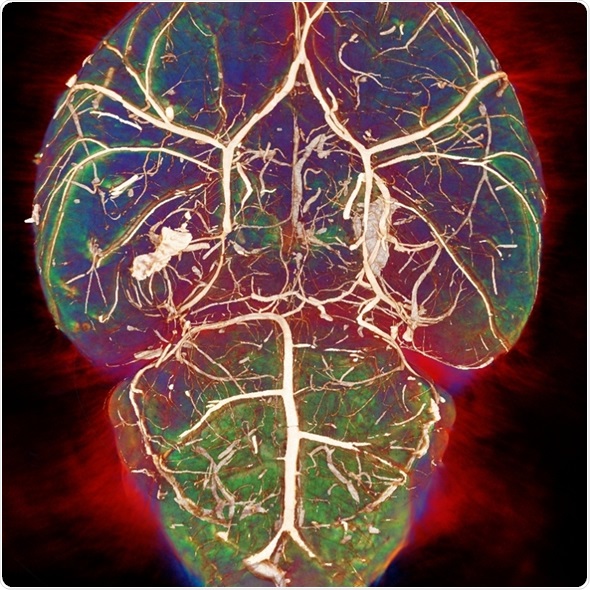

Image credit: Photoacoustic imaging group, UCL